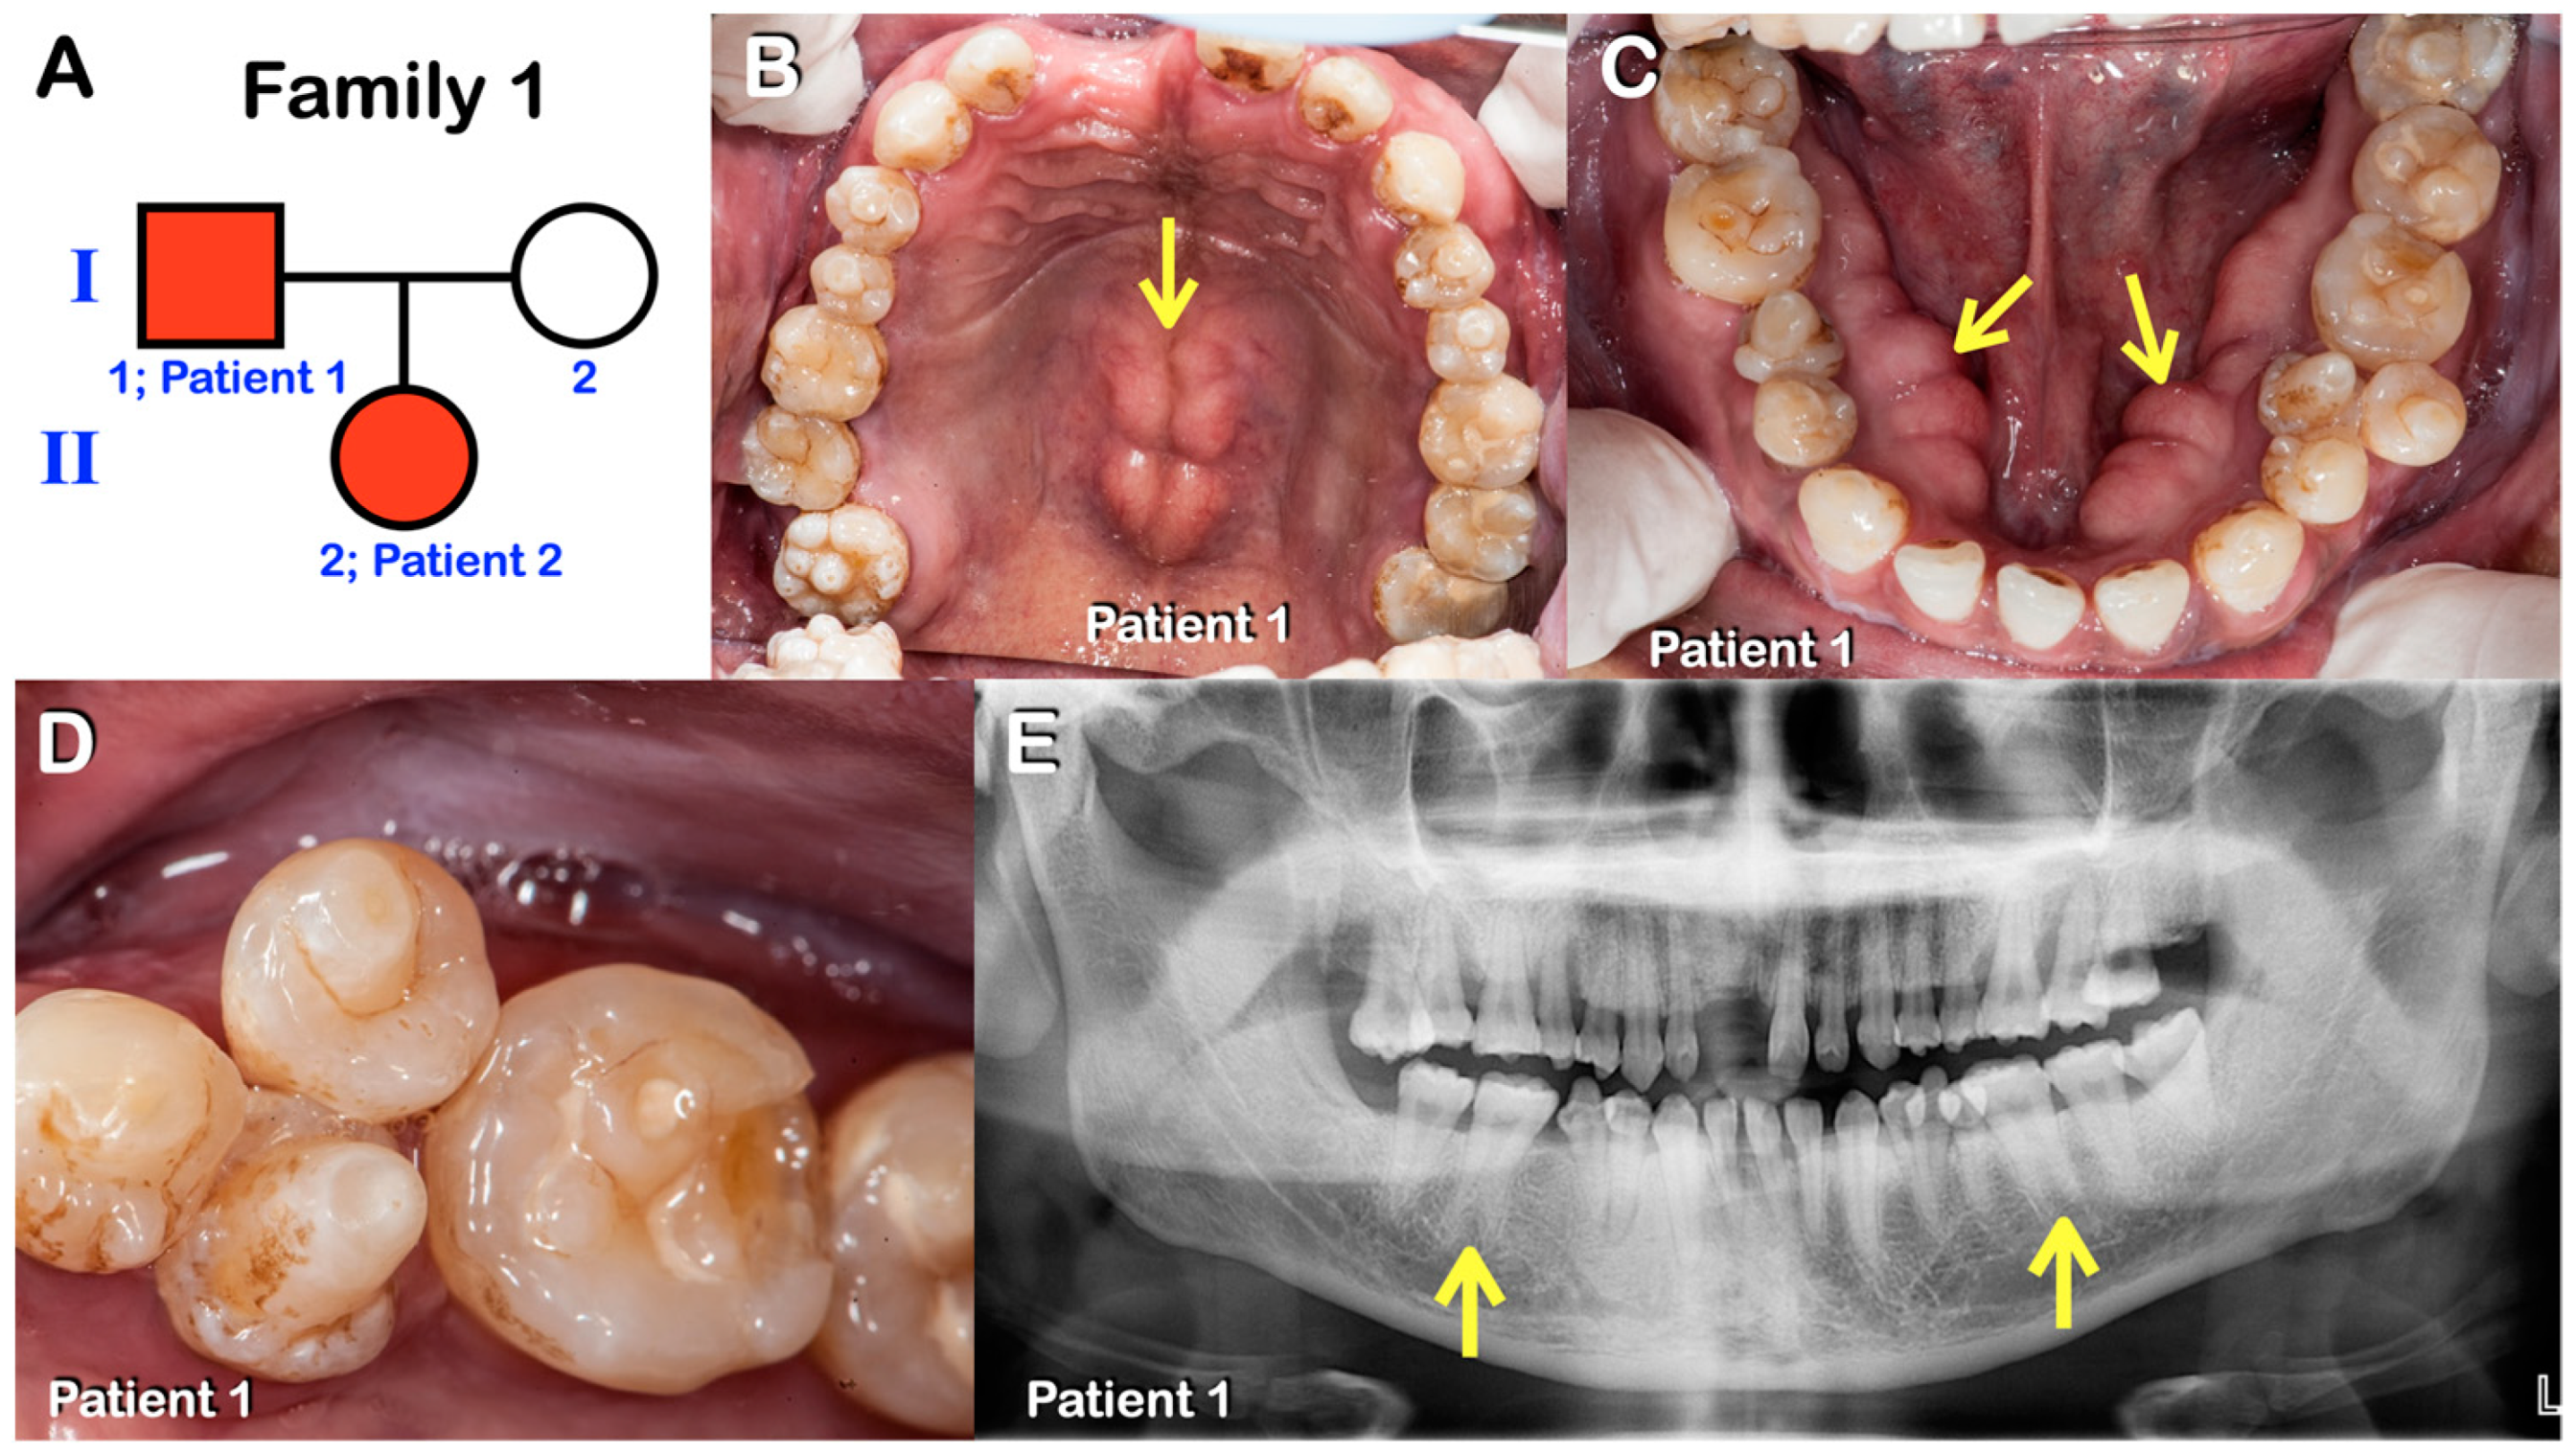

Figure 1.

(A–E) Family 1. (A) Pedigree of family 1. Patients 1 and 2. (B–D) Patient 1. Permanent dentition. Round-shaped permanent molars, molars with multiple supernumerary cusps, premolars with single prominent cusps, torus palatinus (arrow in B), and torus mandibularis (arrows in C). Close-up view of mandibular premolars with single prominent cusps. (E) Panoramic radiograph showing agenesis of the right permanent mandibular third molar, single-rooted permanent molars, and taurodontism (arrows).